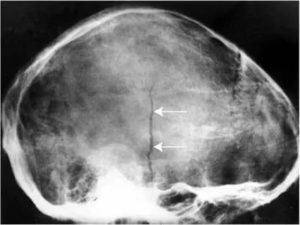

Далее доктор направляет больного на процедуру рентгенографии, которая выполняется в двух проекциях. Если травма является серьезной, то при диагностике тело не меняет своего положения, а передвигается только трубка рентгеновского аппарата.

Томография. Двойной перелом.

Для постановки точного диагноза и составления прогноза выздоровления ребенку проводят рентгенологическое исследование. Краниография позволяет получить четкое изображение, но качественно расшифровать его сможет только опытный врач.

Важно не спутать трещины с сосудистой сеткой и черепными швами. Особенно тяжело отличить трещины, когда они переходят с теменной кости на лобную или затылочную области. Линия разлома имеет черный цвет. Она прямая и узкая без каких либо разветвлений.

При этом сосуды и швы имеют более светлый цвет.

Диагностика перелома теменного сегмента осуществляется с помощью рентгенографического аппарата. Снимок делается в двух проекциях: прямой и боковой.